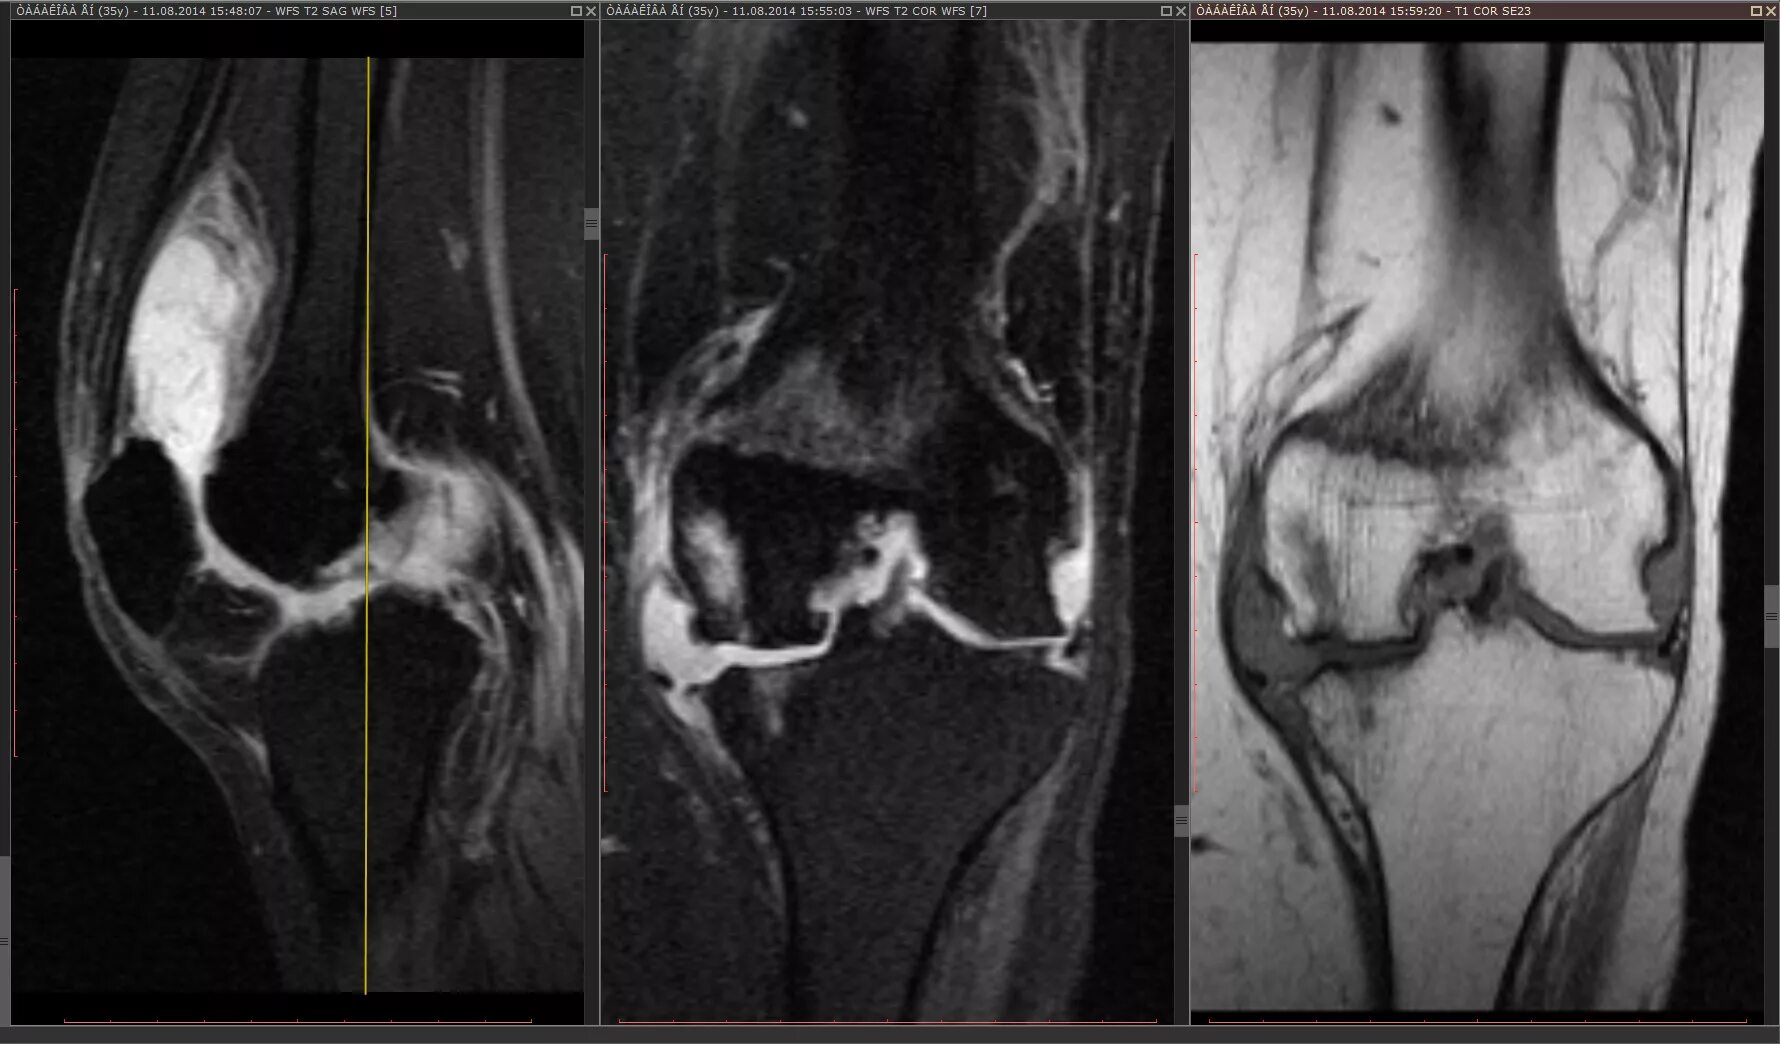

Гонартроз мрт